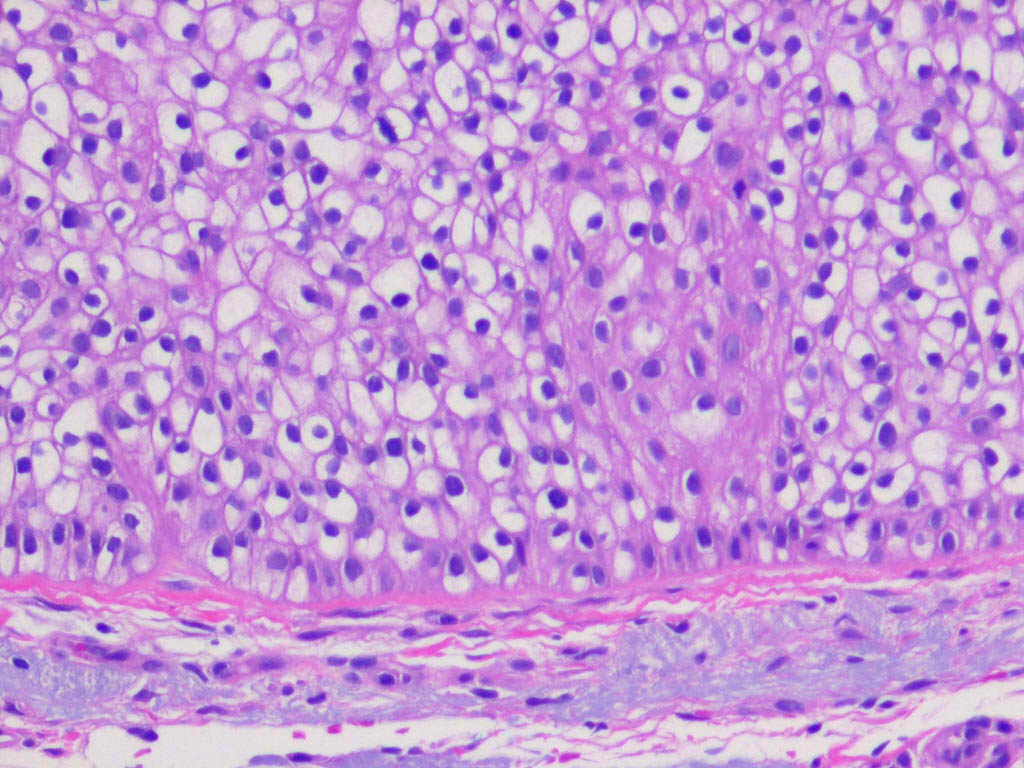

Trichilemmoma =ورم غمد جذر الشعرة